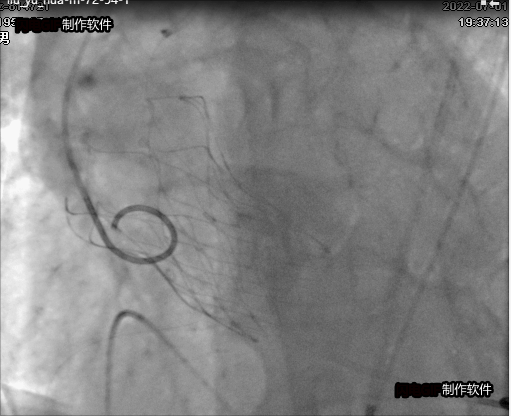

瓣膜植入后最終影像

最終手術(shù)按計(jì)劃進(jìn)行,有效規(guī)避了上述風(fēng)險(xiǎn),順利完成。瓣膜釋放后,患者的主動(dòng)脈瓣跨瓣壓差即由術(shù)前的126mmHg降至16mmHg。次日患者即感胸悶、憋喘癥狀完全緩解,心電圖無(wú)新發(fā)傳導(dǎo)阻滯。目前已順利出院。